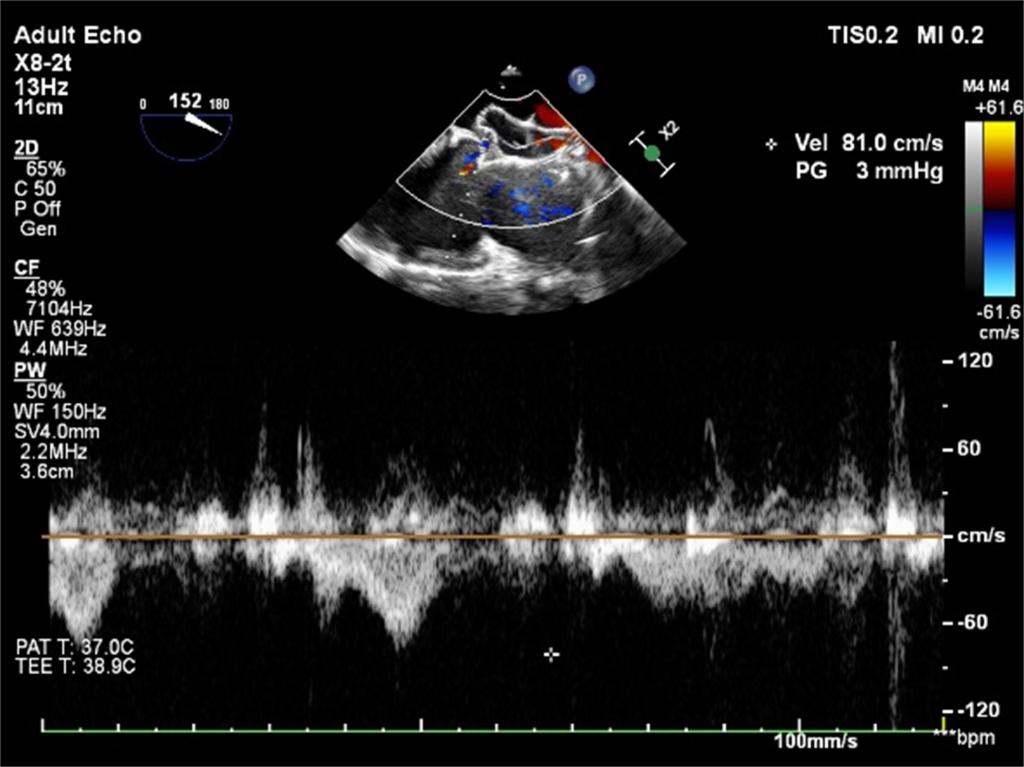

根据手术路径,在全身麻醉后,麻醉医生放置食道超声探头,进行仔细检查,发现患者的房间隔缺损实际有3个。侯江龙教授通过经胸小切口在非体外循环下尝试将较大的两个小缺损融合成一个,然后再用稍大的封堵伞挤压最小的缺损。最终,在术中经食管超声的实时引导下,房间隔缺损封堵术顺利完成,术后几乎无残余分流,避免了开胸和体外循环手术带来的巨大创伤,为患者快速康复提供了坚实的基础。患者术后恢复良好,第二天顺利出院。